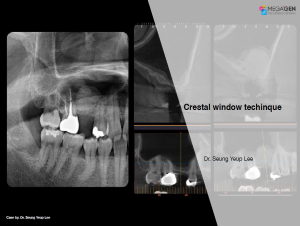

Aesthetic zone,AnyRidge,Clinical case,Dr. Achraf Souayah,Edentulous,Guided surgery,Immediate Placement,Mandibular Anterior,Mandibular Posterior,Maxillary Anterior,Maxillary Posterior,MEG-Rhein,MILA Kit,Overdenture system,Sinus Elevation